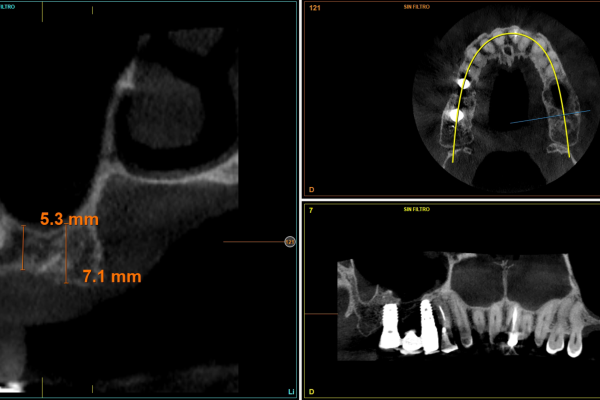

Colocación de implante postextracción con provisionalización inmediata en el sector estético: caso clínico con seguimiento a 4 años